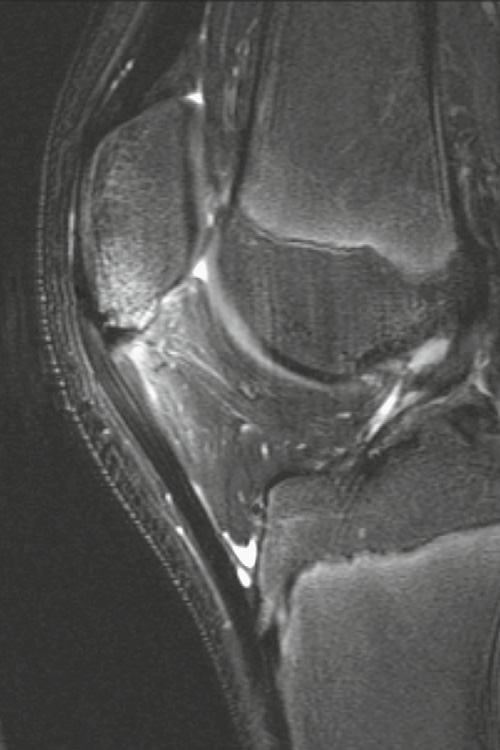

Typical radiographic appearance of JRA of the knee

* joint effusion * epiphyseal overgrowth * widening of the intercondylar notch * accelerated bone maturation

## Footnote Juvenile rheumatoid arthritis of knee. Sagittal, con- trast-enhanced, T1-weighted MR image shows markedly enhanced and thickened synovium. There is an associated joint effusion.